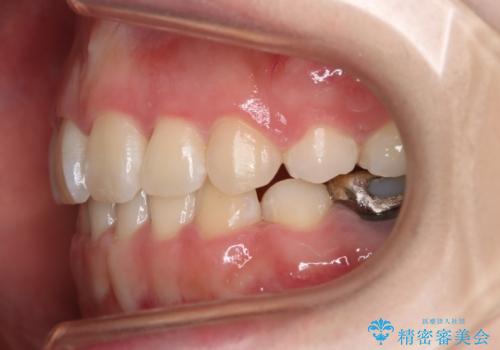

- 前歯のガタつきと口元の改善を主訴に来院されました。

なるべく目立たない装置が良いというご要望と、口元を引っ込めたいというご要望を両方達成するために今回はハーフリンガル装置を選択し治療計画の立案を行いました。

結果的に表の装置よりは期間が掛かりましたが、口元もしっかり下がり韓国美人な横顔になったと患者様にも喜んでいただけました。